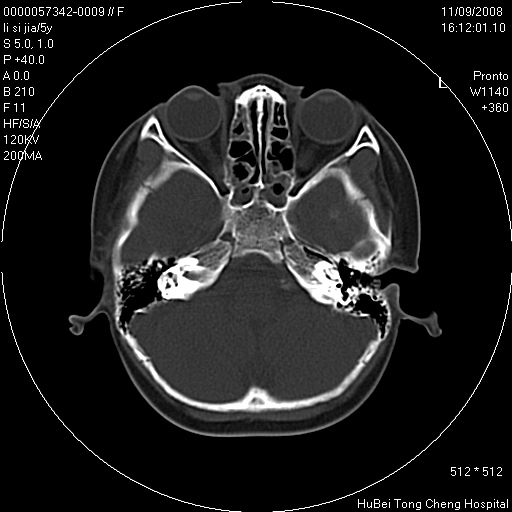

患儿 女,5岁。鼻塞、流涕2年余。

临床诊断:慢性副鼻窦炎?

副鼻窦ct轴位平扫(层厚、层距均为5mm),图像如下:

双侧上颌窦\\筛窦及蝶窦内均可见多量软组织密度影,结合病史支持考虑慢性全鼻窦炎

双侧上颌窦、筛窦及蝶窦内均可见粘膜增厚,结合病史支持考虑慢性全付鼻窦炎,腺样体肥大。